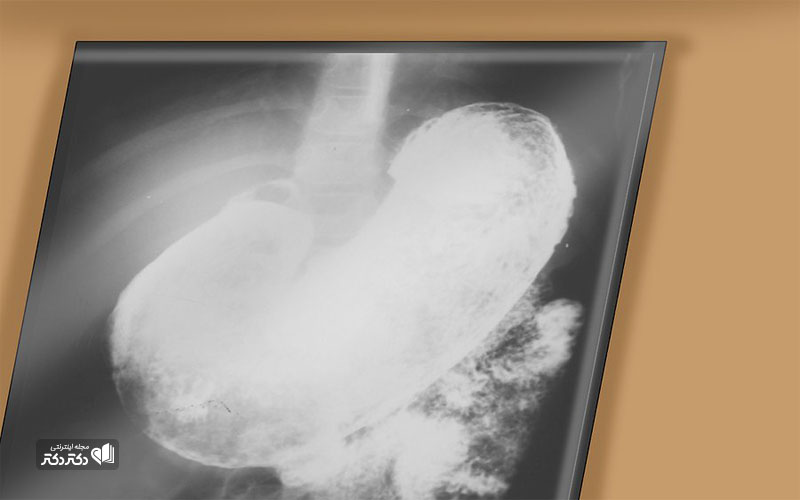

اشعه X از دستگاه گوارش فوقانی. اشعه ایکس تصاویری از مری، معده و روده کوچک را برای جستجوی ناهنجاریها را میدهد.